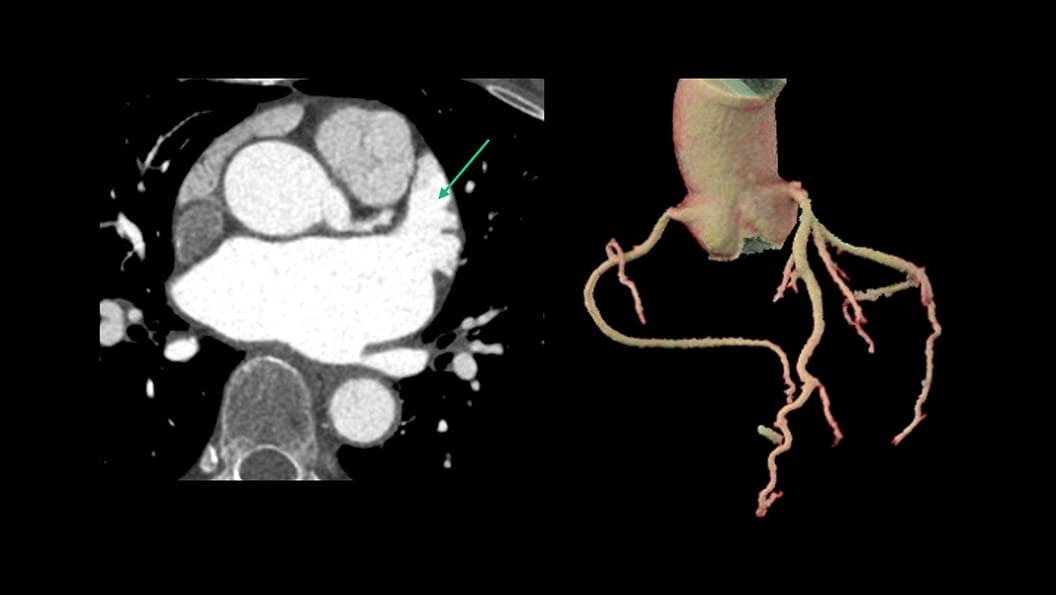

CT-Guided Interventional Care

Since becoming an important step in the patient care pathway and heart care guidelines, CT images are an invaluable tool in the cath lab, guiding procedures for precise personalized care.